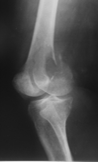

Kemiğin selim-agresif tümörü olarak kabul edilir. Genç erişkinde osteolitik karakterde kemik tümörüdür. Uzun kemiklerin ekleme yakın uç kısmından çıkabilir. Hastalar tümör bölgesinde devamlı ve giderek artan inatçı bir ağrı ve şişlik ile başvururlar.Sadece küretaj yapılan hastalarda yüksek lokal nüks yanında akciğer metastazı yapma potansiyeli olduğundan lokal agresif tümör olarak kabul edilir. Ama bu metastazlar ölümcül değildir.Diz eklemi en sık tutulan bölgedir. Diğer sık tutulan bölge el bileğidir. Kemik korteksini harap ederek yumuşak dokulara yayılım gösterebilir. Tanı için biyopsi şarttır. Brown tümörü ile ayırıcı tanısı yapılmalıdır. Tanı esnasında akciğer tomografisi çekilmelidir.